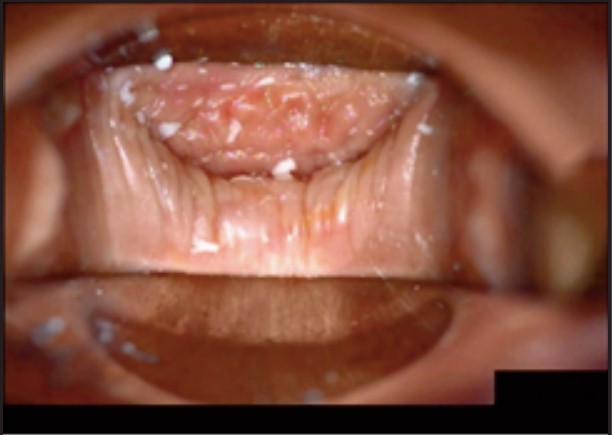

Під час спостереження до та після процедури, через 16 і 36 діб було зроблено вагінальні фотографії за допомогою Tele-Cervico (цервікографія) та виконано порівняння результатів до /після.

У пацієнток 1, 2 і 3 вагінальні складки утворилися та увиразнилися помітніше та сильніше, ніж вони були до лікування, ми оцінили цей клінічний результат після 1-го сеансу (через 16 діб). На нашу думку, такі виразні складки свідчать про підтяжку слизової оболонки піхви, що добре впливає на ущільнення піхви та проблему нетримання сечі. Через 36 діб після процедури ми спостерігали, що зруйнована анатомічна структура піхви відновила Н-подібну форму, тобто стала набагато здоровішою. Зокрема, у пацієнтки 4 структура піхви була цілковито зруйнована, стінки піхви обвисали через втрату еластичності. Однак через 36 днів після процедури структура піхви повністю відновила здорову Н-подібну форму [Див. Малюнок 3].

Пацієнтка №2

До

Після 36 діб

| Результати | √ Відновлено H-подібну структуру √ Збільшено складки √ Дещо зменшилися симптоми SUI |